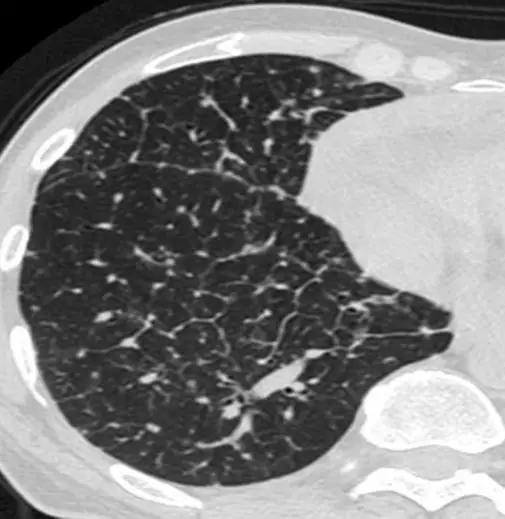

*硬皮病。下叶水平的HRCT表现为混合的“磨玻璃样和网状样”,其特征是磨玻璃样改变和牵引性支气管扩张。请注意5 mm胸膜下不受累,这是硬皮病最常见的组织学类型NSIP的特征相关性肺纤维化。